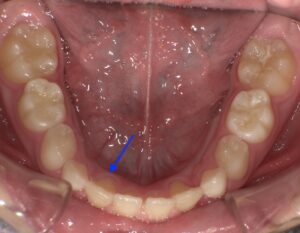

上のアーチが広がり、下の矢印の歯のスペースもできました。

このように比較的軽度に拡大してくれればいい場合に適していると思います。